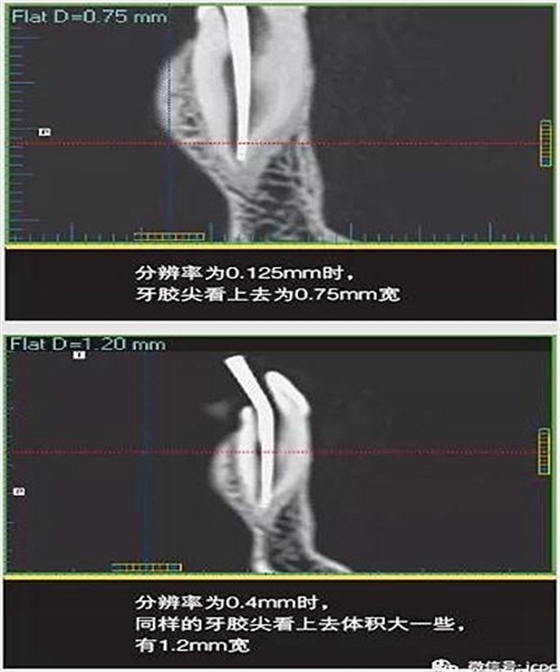

如果探測(cè)器中一個(gè)高對(duì)比度物體的體積小于體素尺寸,則該對(duì)象將會(huì)有效地填充入整個(gè)體素,使其看起來(lái)比實(shí)際物體大。牙膠周邊碎片的顯影就是其中一個(gè)很好的例子,如果牙膠周邊碎片的體積小于體素大小,則圖像上會(huì)看起來(lái)比實(shí)際的大。